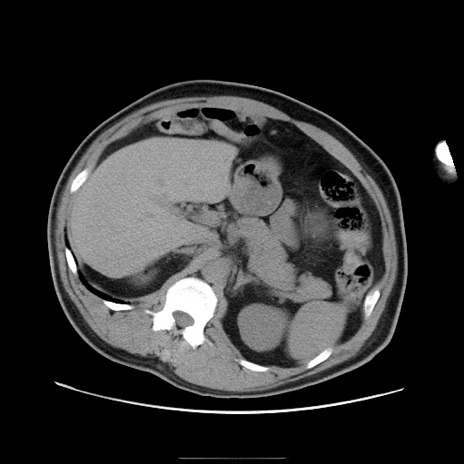

症例22(横断像)

【症例】50歳代男性

【主訴】腹痛

【現病歴】AVMからの被殻出血のため回復期リハ病棟入院中。 本日午後3時頃急に下腹部痛が出現した。

【既往歴】AVM、被殻出血、虫垂炎、高血圧

【身体所見】意識晴明、左半身不全麻痺、会話の理解は良好、36.5°C、腹部:膨隆、全体に板状硬、下腹部正中に圧痛点あり、反跳痛-、筋性防御不明、右下腹部にope scar

【データ】WBC 9400、CRP 0.06